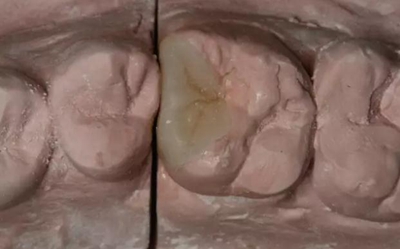

患者女性,55歲,3年前B3纖維樁+鑄瓷全冠修復(fù),一周前牙冠折斷,就診后,發(fā)現(xiàn)纖維樁根管口處折斷,周圍牙齦增生,建議患者行冠延長(zhǎng)手術(shù)。首先去除斷端的纖維樁。拍片示牙根長(zhǎng)度充足。于是開始冠延長(zhǎng)手術(shù)。

因?yàn)槭乔把?,故該患者將?lái)修復(fù)體邊緣必須為齦下,所以3個(gè)月后再行修復(fù)。以下為手術(shù)前照片。